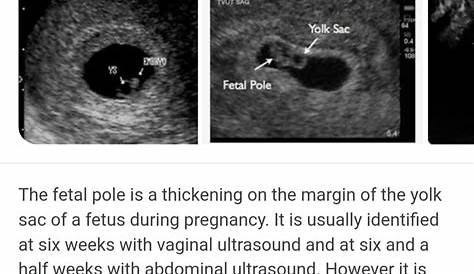

Сосредоточившись на беременных женщинах с синдромом Марфана, Ma et al. Они обнаружили беременность, нашли гестационный мешок, небольшое кровотечение в плаценте и отсутствие фетального полюса. Они видели гестационный мешок и желточный мешок, но не фетальный полюс или сердцебиение.

Полоса плода — это утолщение в центре эмбриона, обычно видимое на ультразвуке между 5 и 7.

Здравствуйте, пошли на трансвагинальное сканирование в 6+6 и они могли видеть гестационный сак+йоу, но не плодного полюса. Я слышал о каком-то плодном полюсе, не показывающемся в 6 недель из-за ретровертированной матки, поэтому он может применяться и в 7 недель. Мой врач говорит, что, возможно, выкидыш или, возможно, слишком рано. Доктор делает УЗИ сказал, что он может видеть гестационный мешок и желток, но нет плодного полюса.

Если ваш мешок беременности имеет размеры 25 мм или более, он должен содержать небольшой эмбриональный столб / ребенка.